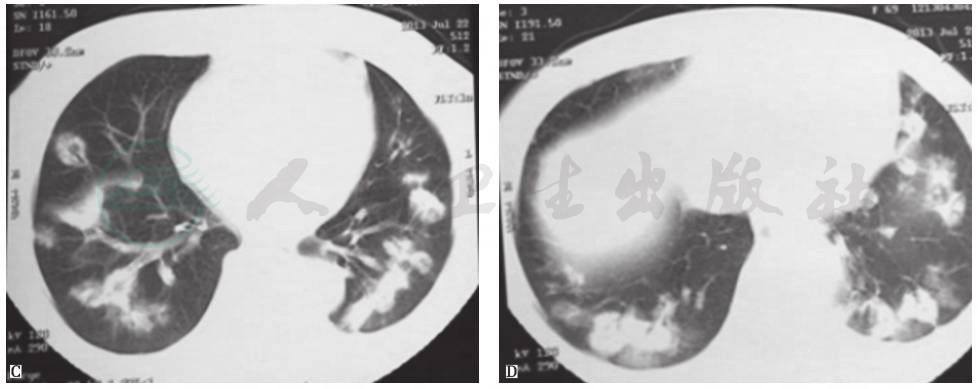

胸部CT:两肺见散在多个片状、花环状高密度影,反晕征,部分密度不均,边缘尚清,部分相互融合,大部分可见含气支气管征(图7)。

图7 入院后胸部CT表现(发病第50天)

患者入院后所做系列检查显示:①肿瘤标志物及大便检查均阴性,结合临床表现,基本上可排除胃肠道肿瘤肺转移;②虽然抗核抗体为1∶100,但其余自身抗体均阴性,结合临床表现,暂不考虑风湿免疫病;③胸部CT提示病变进一步加重;④常规病原学检查均阴性。因此,不排除曲霉菌感染的可能。但患者应用伊曲康唑治疗10天后,复查胸部CT(图8)提示病情进一步加重,且静息状态下动脉血气呈现低氧血症(FiO2 33%,PaO2 64mmHg)。由此推测,本病例可能是由一些非感染非肿瘤性疾病引起。

图8 入院后胸部CT表现(发病第58天)

胸部CT显示,与发病第50天时(图7)相比,双肺原有病灶进一步加重,并出现右侧少量胸腔积液

患者经口服糖皮质激素抗炎治疗后稳定恢复,复查胸部CT见图10~图12。

图10 治疗8天时胸部CT表现

胸部CT见双肺原有病灶明显吸收,胸腔积液消失

图11 治疗22天时胸部CT表现

胸部CT见双肺原有病灶明显吸收,部分病灶完全吸收

图12 治疗3个月时胸部CT表现

胸部CT见双肺原有病灶完全吸收消失

图13 隐源性机化性肺炎胸部CT表现

女性患者,64岁,咳嗽、间断发热4个月余。胸部CT见右肺多叶段高密度实变影,右下肺膨胀不全伴轻度反晕征